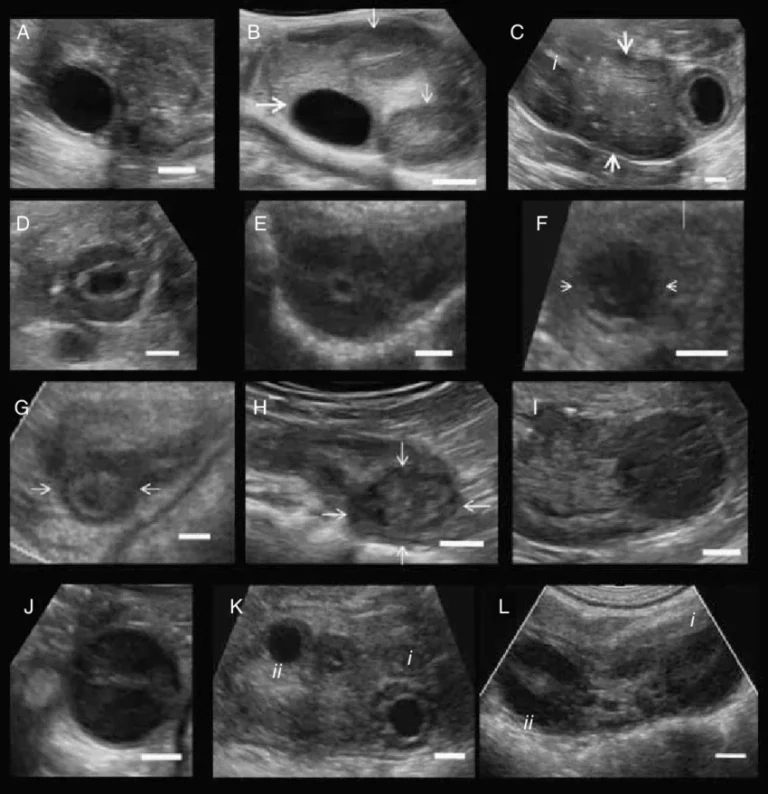

Ovulation study is performed using transvaginal ultrasound (TVS), which provides clear and accurate images of the ovaries and uterus.

4. Ovulation Detection

• A mature follicle (18–24 mm) ruptures

• Indicates egg release

5. Post-Ovulation Confirmation

• Fluid in pelvis confirms ovulation